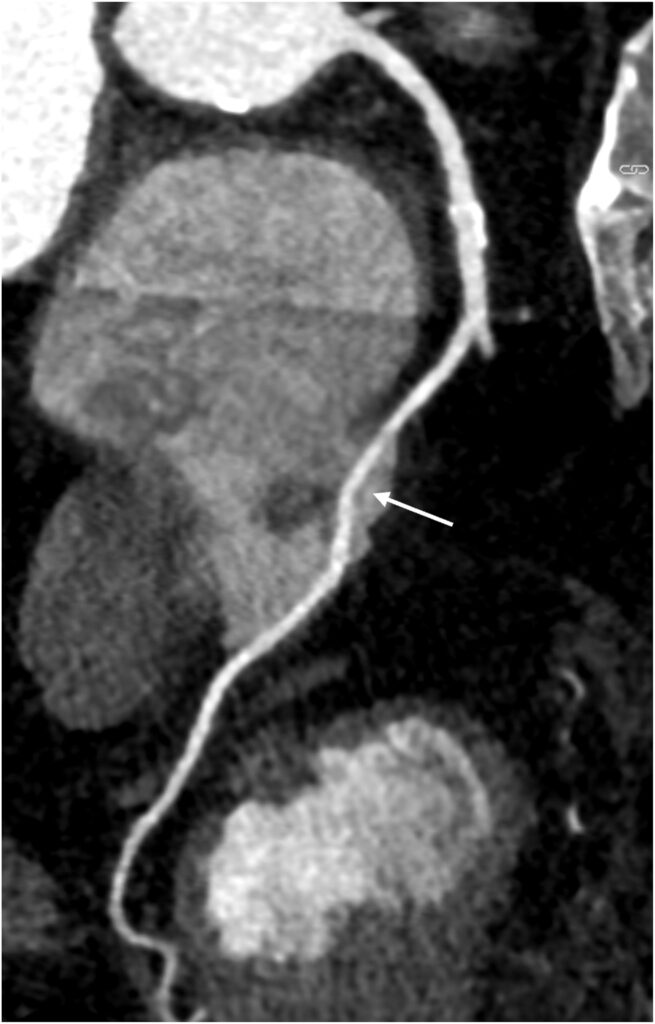

O exame mostrou origens normais tanto da CD quanto da coronária esquerda, com presença de lesão aterosclerótica com estenose moderada na DA, bem como confirmou a suspeita de trajeto anômalo da CD, com o seguimento médio apresentando curso intra-atrial transversal de 3.5 cm.

Posteriormente, o paciente foi submetido a cateterismo cardíaco que confirmou a presença de lesão moderada no terço médio da DA enquanto que a CD não apresentava lesões ateroscleróticas. O paciente recebeu alta sob tratamento clínico direcionado.